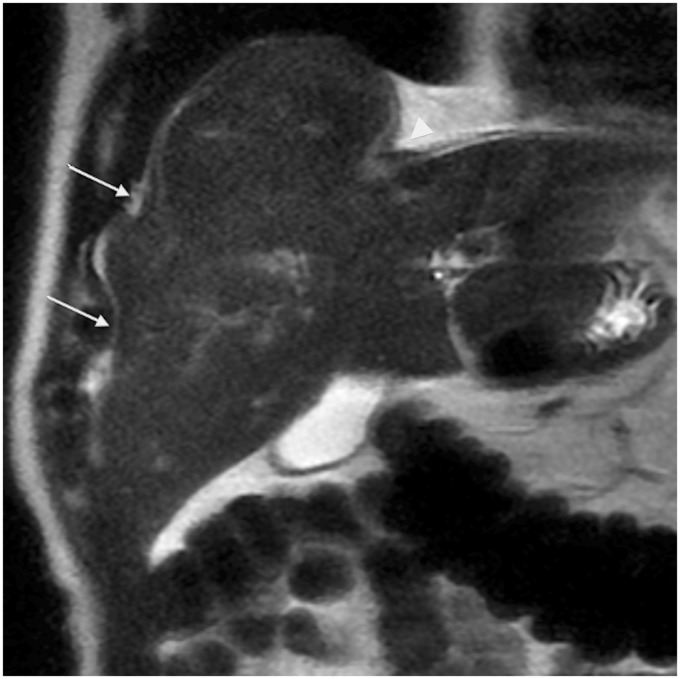

Hepatic capsular retraction is an imaging feature that deserves the attention of the radiologist. Hepatic capsular retraction is associated with a number of hepatic lesions, benign or malignant, treated or untreated. The purpose of this pictorial review is to discuss the most common benign and malignant hepatic lesions associated with this feature with an emphasis on magnetic resonance imaging (MRI).